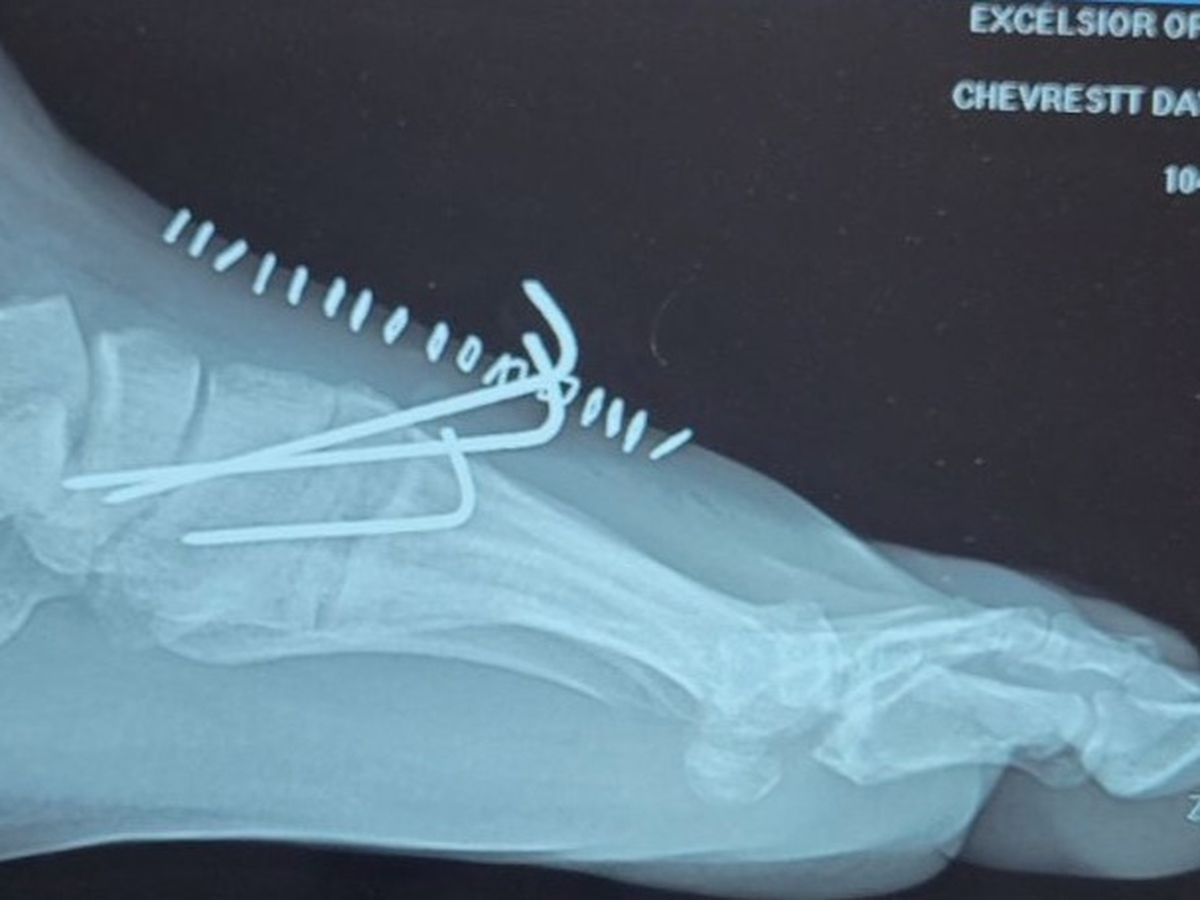

While playing in a Not Very Important game of recreational softball - stone-cold sober of all things - our friend David (Dave if you're an O.G.) managed to fracture 3 bones in his mid-foot sliding into home plate.